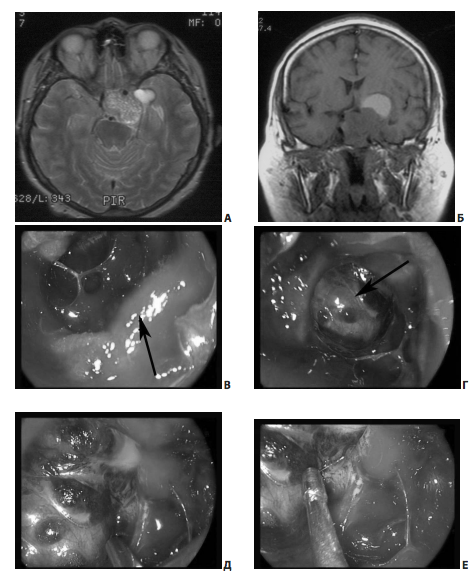

В ряде случаев от верхнего полюса кавернозного синуса отходят вторичные узлы опухоли, которые также доступны для удаления во время эндоскопического вмешательства (рис. 8).

Рис. 8. Пример удаления эндо-супра-латероселлярной аденомы (от кавернозного синуса отходит вторичный узел опухоли): А, Б — МРТ до операции; В — интраоперационное фото; стрелкой указано переднее колено левой сонной артерии; Г — интраоперационное фото; стрелкой указана полость вторичного узла; Д, Е — интраоперационное фото; этапы удаления опухоли из полости вторичного узла